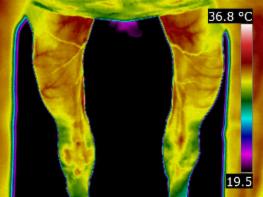

I offer trainers, riders and owners the benefit of monitoring their horses for injury and trauma during training and performance. Infrared imaging will safely and quickly identify areas of interest enabling you to adjust the training regime to reduce stress and help prevent injury. There is an increase in horses being monitored during training in this way. | |

As a form of “preventative medicine”, thermography has proven to be extremely valuable. After an Initial Scan which acts as our baseline data, we can compare periodic images. These regular thermal imaging scans can show up changes and irregularities that may be addressed and rectified, by management or treatment, before any actual damage has taken place. | |

Thermography also can predict and monitor joint inflammation. Normally cool joints might change their thermal pattern before the onset of lameness. The damaged joint can be detected due to the thermal pattern. The practitioner can then use thermography to monitor the effect of treatments. |